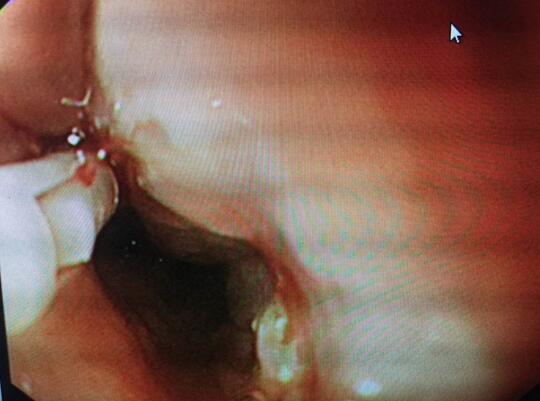

内镜中心王莹副主任考虑到患者病情复杂且高龄,不具备急诊外科手术条件,在确保患者安全情况下行内镜下异物钳取术、钛夹封闭损伤治疗。术中观察到梭形枣核嵌顿于患者食管上端,一侧食管壁可见纵形全层伤口,损伤非常严重。王主任克服困难,以她熟练的操作最终将异物顺利取出。

患者术后病情逐渐好转。第6天复查上消化道造影无食管龛影及造影剂无食管外漏,随后饮食从糊状流食逐渐过渡到正常,术后16天,患者饮食正常,无特殊不适,康复出院。通过本次内镜治疗,即减轻患者开胸术过程中的医源性创伤、痛苦、甚至危及生命的风险,又减轻了患者家庭的经济负担。患者及家属非常感激,多次向科室表示感谢。

钛夹完全夹闭损伤